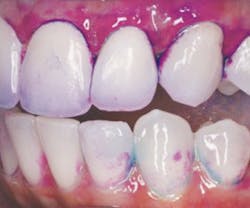

Figure 2: F.L.A.G. fluoresces plaque biofilm with the Newtron LED light.

Acteon combines a novel method of disclosing and fluorescing plaque biofilm that relies on its Newtron B LED ultrasonic handpiece to fluoresce it. The fluorescent disclosing liquid, called F.L.A.G., identifies plaque bacteria and fluoresces with the handpiece's blue LED light as seen in Figure 2. Calculus does not fluoresce; it stains orange or yellow. HurriView and HurriView II are single-use, cellophane-packaged, prefilled Snap-N-Go swabs that contain either red dye or two-tone red and blue dy. With this you can quickly see what you're up against with biofilm management.